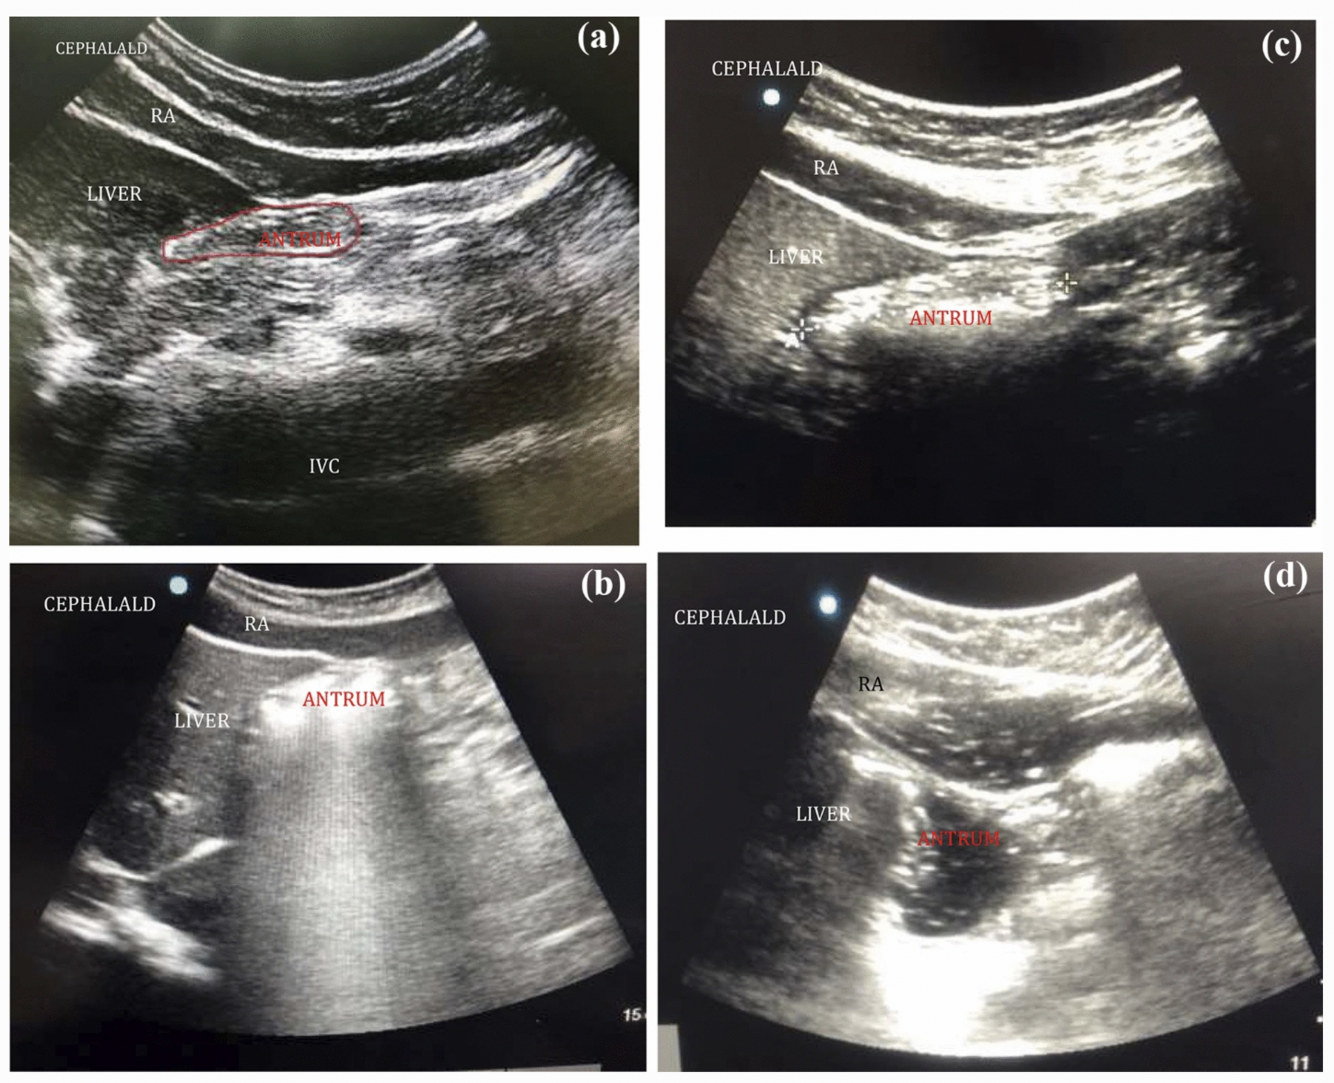

Gastric USS image - what is picture A

a) Empty stomach

b) full stomach (early)

c full stomach (late)

d ) fluids

A

A: empty stomach